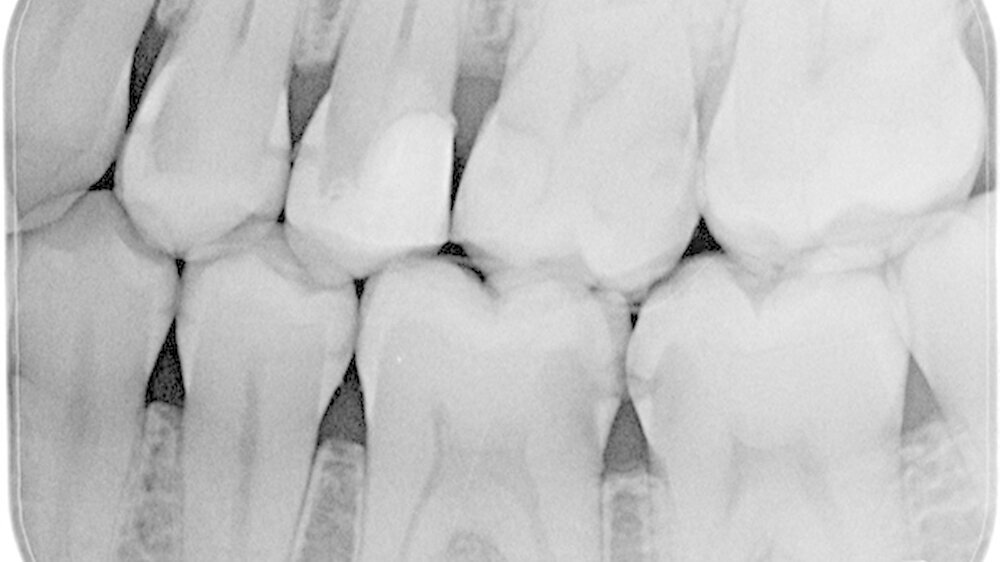

Zuerst ist fast immer der Vierer distal betroffen, dann folgt der Fünfer mesial. Milchzähne haben durchschnittlich nur eine Schmelzdicke von einem Millimeter, der Schmelz am Vierer distal ist noch dünner, das heißt noch anfälliger. Der Kontaktpunkt 4/5 bildet sich erst in der Gebrauchsphase des Milchgebisses, wobei er zusätzlich häufig flächiger wird. Die anderen Kontaktpunkte im Milchgebiss lösen sich durch die physiologische Lückenbildung eher auf, das Kontaktpunktkariesrisiko sinkt also.

Wie wichtig ist die Bissflügelaufnahme für die Diagnose?

Ich mache immer mehr Bissflügelaufnahmen und immer früher. Denn erkenne ich eine initale Karies früh, kann ich diese mit den Eltern zusammen ausheilen, sprich eine Füllung beziehungsweise abhängig vom Alter und der Kooperationsbereitschaft des Kindes eine Sanierung in Narkose verhindern. Das Röntgenbild zeigt den Eltern das Problem und hilft mir, sie für die Verwendung von Zahnseide zu gewinnen.